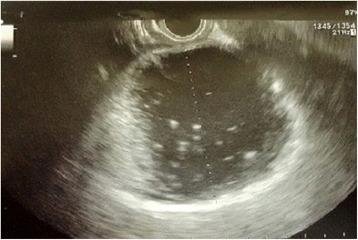

We describe a case of a 64-year old man with large multiple pancreatic cysts discovered for progressive jaundice and significant weight loss in the absence of a previous episode of acute pancreatitis. Computed tomography scan showed lesion with thick enhancing walls. The main cyst dislocated the stomach and the duodenum inducing intra and extrahepatic bile ducts enlargement. Magnetic resonance cholangiopancreatography revealed a communication between the main pancreatic duct and the cystic lesions due to Wirsung duct rupture. Endoscopic ultrasound guided fine needle aspiration cytology did not show neoplastic cells and cyst fluid analysis revealed high amylase concentration. Preoperative exams were suggestive but not conclusive for a benign lesion. Laparotomy was necessary to confirm the presence of large communicating pseudocysts whose drainage was performed by cystogastrostomy. Histology confirmed the inflammatory nature of the cyst wall. Subsequently, the patient had progressive jaundice resolution.

我们描述了一例64岁男性,因进行性黄疸和显著体重减轻发现多个巨大胰腺囊肿,既往无急性胰腺炎发作史。计算机断层扫描显示病变壁增厚且强化。主囊肿使胃和十二指肠移位,导致肝内和肝外胆管扩张。磁共振胰胆管造影显示由于主胰管破裂,主胰管与囊性病变之间存在连通。内镜超声引导下细针穿刺细胞学检查未发现肿瘤细胞,囊液分析显示淀粉酶浓度高。术前检查提示为良性病变,但不能确诊。需要进行剖腹手术以确认存在巨大的连通性假性囊肿,并通过囊肿胃吻合术进行引流。组织学证实囊肿壁具有炎症性质。随后,患者的黄疸逐渐消退。